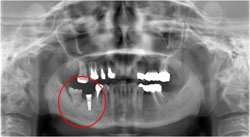

抜歯を行い、歯を抜いた部分が凹むのを防ぐために人口の骨をいれました。

インプラントの施術前の診断として、どのくらいの長さの

インプラントを用いるか測定を行います。